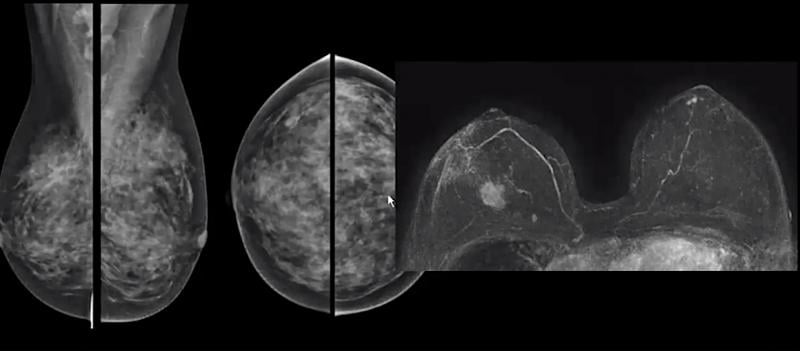

The current body of research supporting digital breast tomosynthesis (DBT or 3-D mammography) is now overwhelming, with ...

The incidence of breast cancer is rising globally, with an estimated 1 in 8 women diagnosed in their lifetime and 40,000 ...